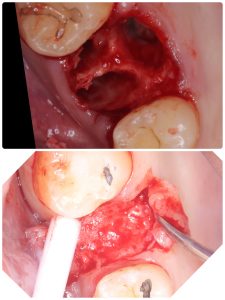

昼間からは、危ない動脈近接のソケットリフト

バッチリ👍避けるコツがある💪

抜歯後2ヶ月待ちオペ、EMDとボナークのお陰です

5ミリで骨折、自己採血2本メンブレン挿入